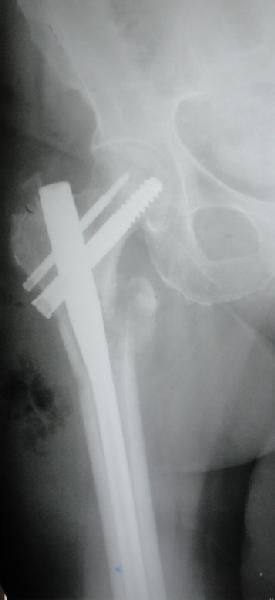

Фиксация * reversed obliquity* подвертельных переломов - дело непростое.

На мой взгляд, причиной телескопирования явилось несоответствие диаметра гамма нэйл с диаметром канала подвертельного отдела бедра: обратите внимание на величину протрузии шеечного винта и величину медиализации дистального фрагмента - они одинаковы, смещение или телескопирование фрагментов происходило до того момента, пока гамма нэйл не упёрся в медиальный кортекс и образовалось пространство между латеральным

кортексом и латеральной поверхностью гвоздя.

E> На мой взгляд, причиной телескопирования явилось несоответствие

E> диаметра гамма нэйл с диаметром канала подвертельного отдела бедра:

Диаметр гаммы в диафизарной части ~11 мм. А диаметр канала, тем более у пожилых с остеопорозом, может быть мм 15. Даже рассверливать обычно не приходится, после формирования широкого канала в вертельной области можно сразу толкать гвоздь, он влетает, как карандаш в стакан. Так что соответствия диаметров не бывает никогда. Однако представленная ситуация случается далеко не каждый раз. Если гвоздь в центральном отломке входит чуть медиальнее верхушки вертела, и идет вдоль передне-латеральной стенки центрального отломка, то все будет хорошо.

В приложении похожий пример, к счастью, пациентка появилась не после, а "за полчаса" до протрузии. Пересинтезировали с исправлением ошибок.